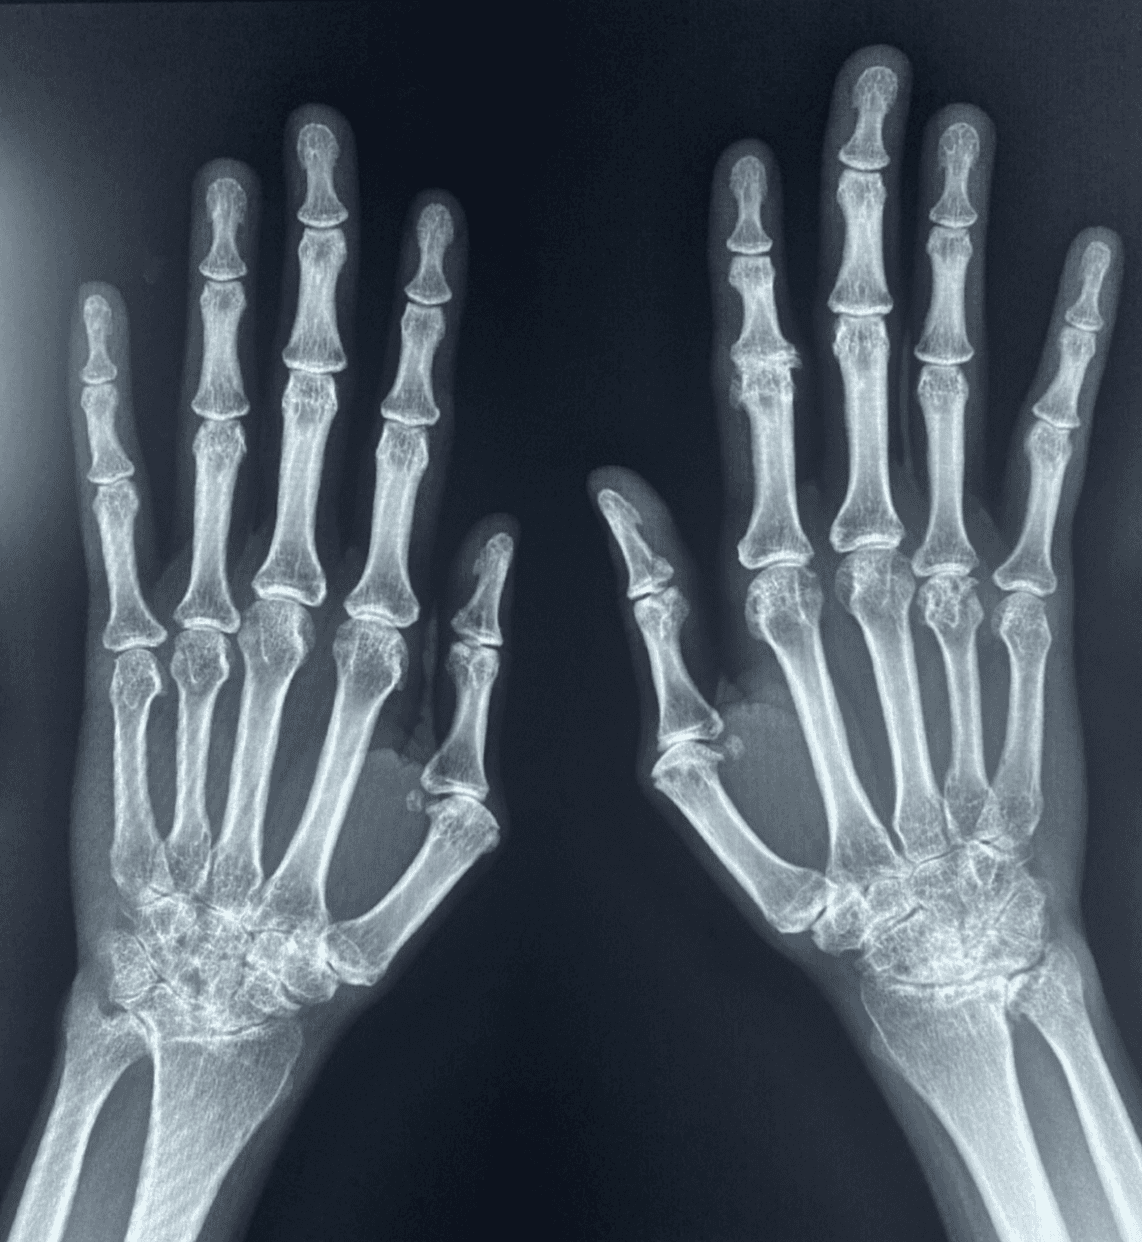

En artritis reumatoide, el patrón clásico combina tumefacción fusiforme y simétrica de partes blandas, osteopenia yuxtaarticular, erosiones marginales tempranas en cabezas metacarpianas y bases proximales de falanges, progresión a pinzamiento articular uniforme y deformidades por inestabilidad ligamentaria, como subluxación cubital en MCP. La preservación relativa de las articulaciones DIP es una pista mayor. En artritis psoriásica, por el contrario, la mineralización suele mantenerse, predominan las interfalángicas, la dactilitis aparece en cerca del 25% de los pacientes y las erosiones marginales progresan a deformidad tipo pencil-in-cup; además, la periostitis y la proliferación ósea ayudan a separarla de artritis reumatoide. La osteoartrosis erosiva, frecuente en mujeres mayores de 60 años, muestra erosiones centrales con configuración en gull-wing o seagull, con afectación predominante de DIP y respeto habitual de MCP. La artropatía por CPPD introduce otro lenguaje: condrocalcinosis en fibrocartílago triangular y ligamentos del carpo, osteofitos en gancho en la segunda y tercera cabezas metacarpianas y cambios degenerativos en una distribución no típica para osteoartrosis primaria. La gota, en cambio, combina masas de partes blandas por tofos, mineralización conservada, erosiones bien definidas con borde escleroso y márgenes colgantes; además, los cambios radiográficos pueden tardar en aparecer en promedio entre 7 y 10 años. Finalmente, el lupus eritematoso sistémico suele manifestarse con subluxaciones y deformidades reducibles sin erosiones, mientras que en esclerosis sistémica la acroosteólisis y las calcificaciones de partes blandas dominan la imagen.

La tabla comparativa del artículo resume una idea central: cada entidad tiene una geografía preferente. La artritis reumatoide predomina en MCP y carpo, con afección inusual de las DIP; la artritis psoriásica compromete sobre todo interfalángicas y con frecuencia las DIP; la osteoartrosis erosiva se concentra en interfalángicas, especialmente DIP; la CPPD favorece MCP y radiocarpiana en una distribución “incorrecta” para osteoartrosis primaria; la gota puede ser poliarticular asimétrica con masas tofáceas y erosiones bien definidas; y el lupus típicamente produce deformidad sin erosión. En otras palabras, el primer paso del diagnóstico diferencial no es la erosión, sino el mapa articular.

Uno de los aportes más útiles del artículo es recordar la lectura sistemática con el esquema ABCDES: alineación, huesos, cartílago, densidad mineral, erosiones y partes blandas. Esta secuencia obliga a evaluar subluxaciones y desviaciones; destrucción ósea o lesiones; pérdida de espacio articular; osteopenia focal o difusa; patrón erosivo; y tumefacción o calcificaciones. Más que una regla mnemotécnica, funciona como una forma de traducir una imagen aparentemente sencilla en un razonamiento radiológico reproducible. En enfermedades inflamatorias, omitir un solo componente puede cambiar la interpretación: una erosión marginal en MCP no pesa igual que una erosión central en DIP; una mano con disminución de mineralización no cuenta la misma historia que otra con mineralización conservada y proliferación ósea.